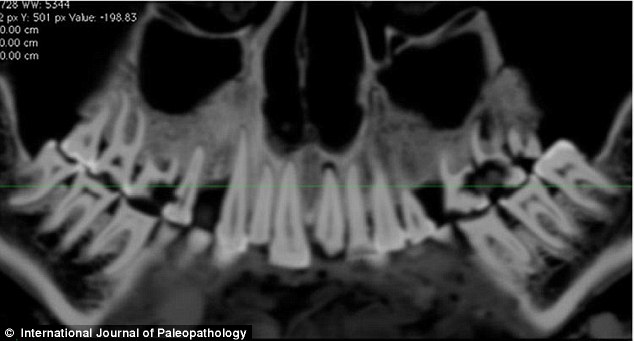

上图是木乃伊口腔CT扫描图,可以看到亚麻布团被填充在右部。

《古病理学国际期刊》的文章称,来自加拿大西安大略大学的安德鲁·韦德利用一种新型高分辨率CT仪扫描木乃伊的牙齿和身体,并且根据扫描片重建了3D图以进行更为细致的研究。从CT扫描片可以看到,木乃伊的一颗牙齿龋洞里塞着一块亚麻布团。这块亚麻布之前可能经过无花果汁液或雪松油等药物的浸泡,随后被塞入下颚第一、二颗臼齿中间,也就是最大、也是最疼的龋洞里。这么做既能起到抵挡食物残渣进入龋洞的屏障作用,又能利用亚麻布上的药物缓解疼痛。

早在20世纪90年代中期,就有研究人员发现了木乃伊口中的小麻布团,但当时的扫描技术太低以至于不能给出更全面的分析,而本次研究使用的高分辨率扫描仪的功能是之前扫描仪的6倍。